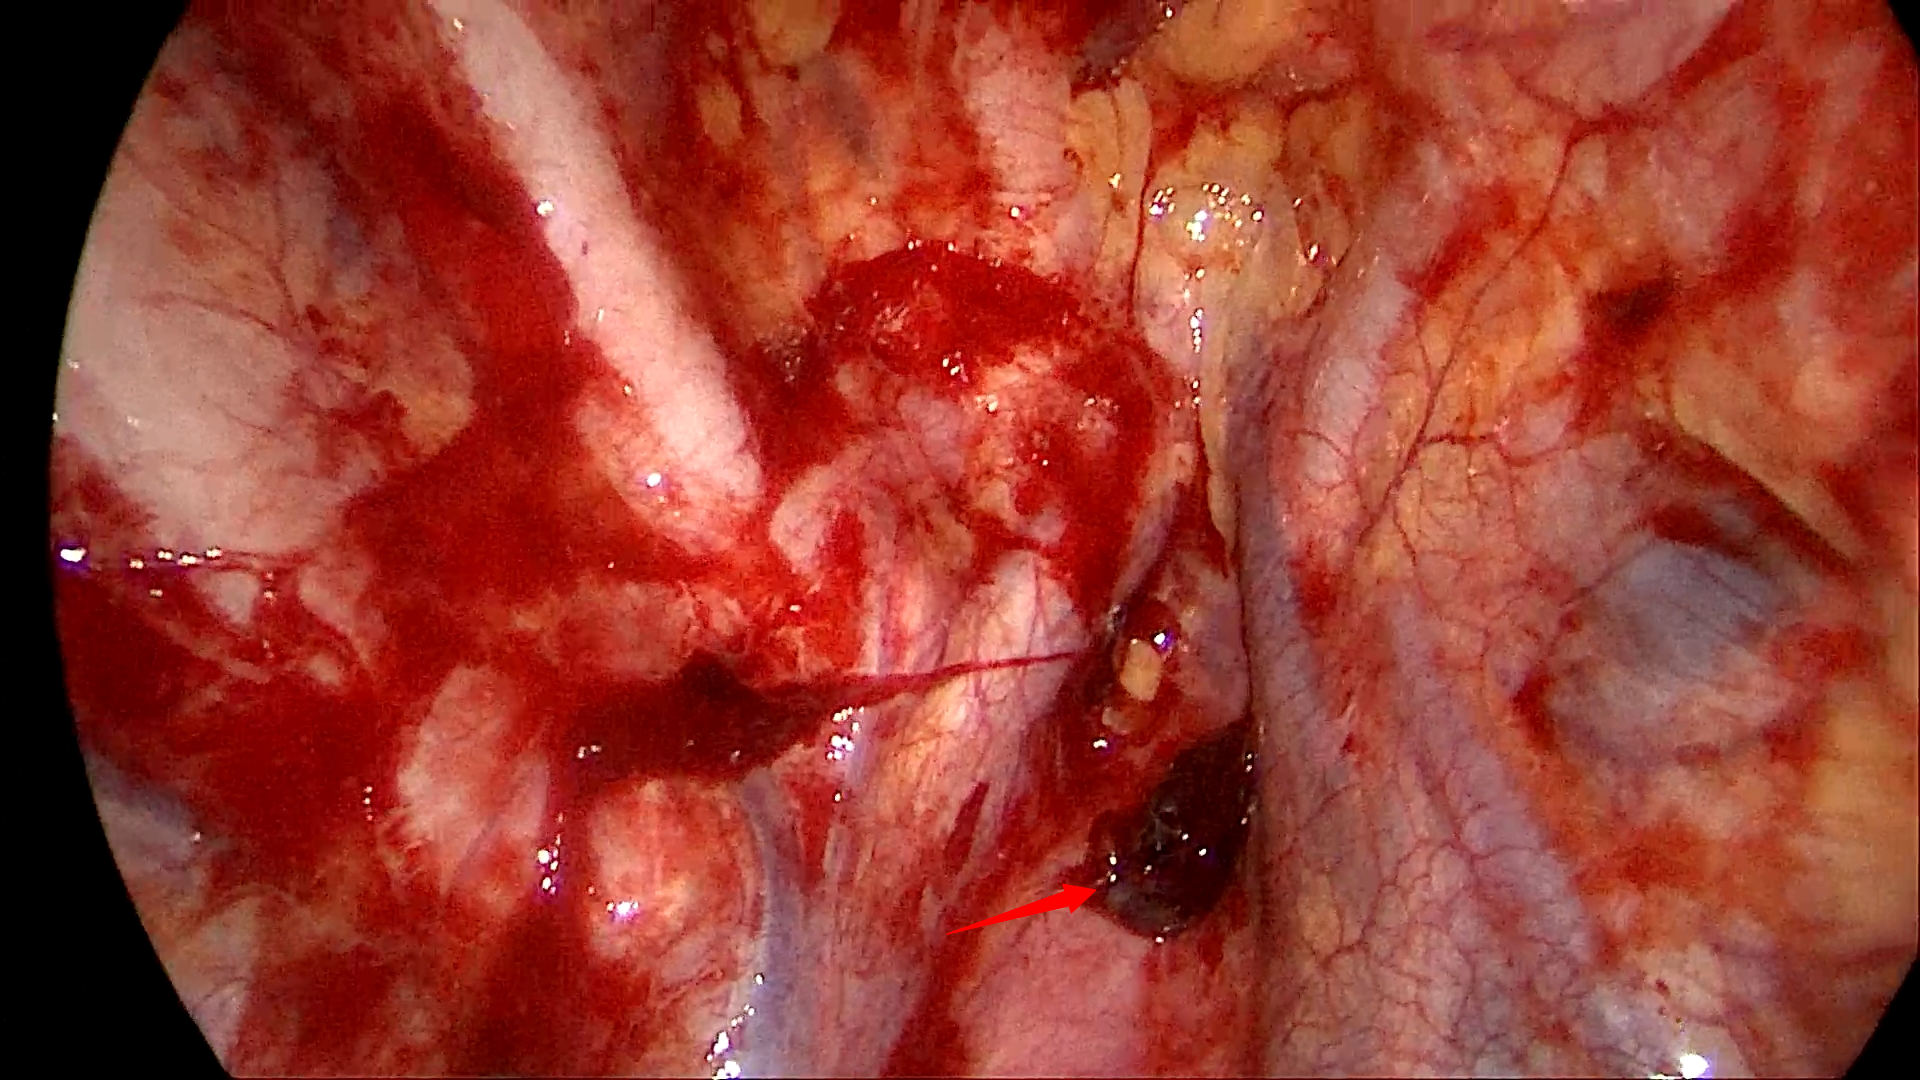

经与患者本人和家属沟通同意后,胸外科团队立即进行手术准备。迅速通知麻醉科、第一手术区紧急做术前准备。崔健会同胸外科副主任医师胡晓丹、赵云,与麻醉科、第一手术区团队共同展开抢救工作。术中,在电视胸腔镜下显示右侧胸腔大量血块,出血点为胸膜顶粘连带(图2),统计出血量达3000ml,术中血液回收机血液置换,一边输血一边进行胸腔镜下止血,右肺肺大疱切除+胸膜固定术。术后患者恢复顺利,术后第2日拔出胸腔引流管,术后第3日顺利出院。

▲图二